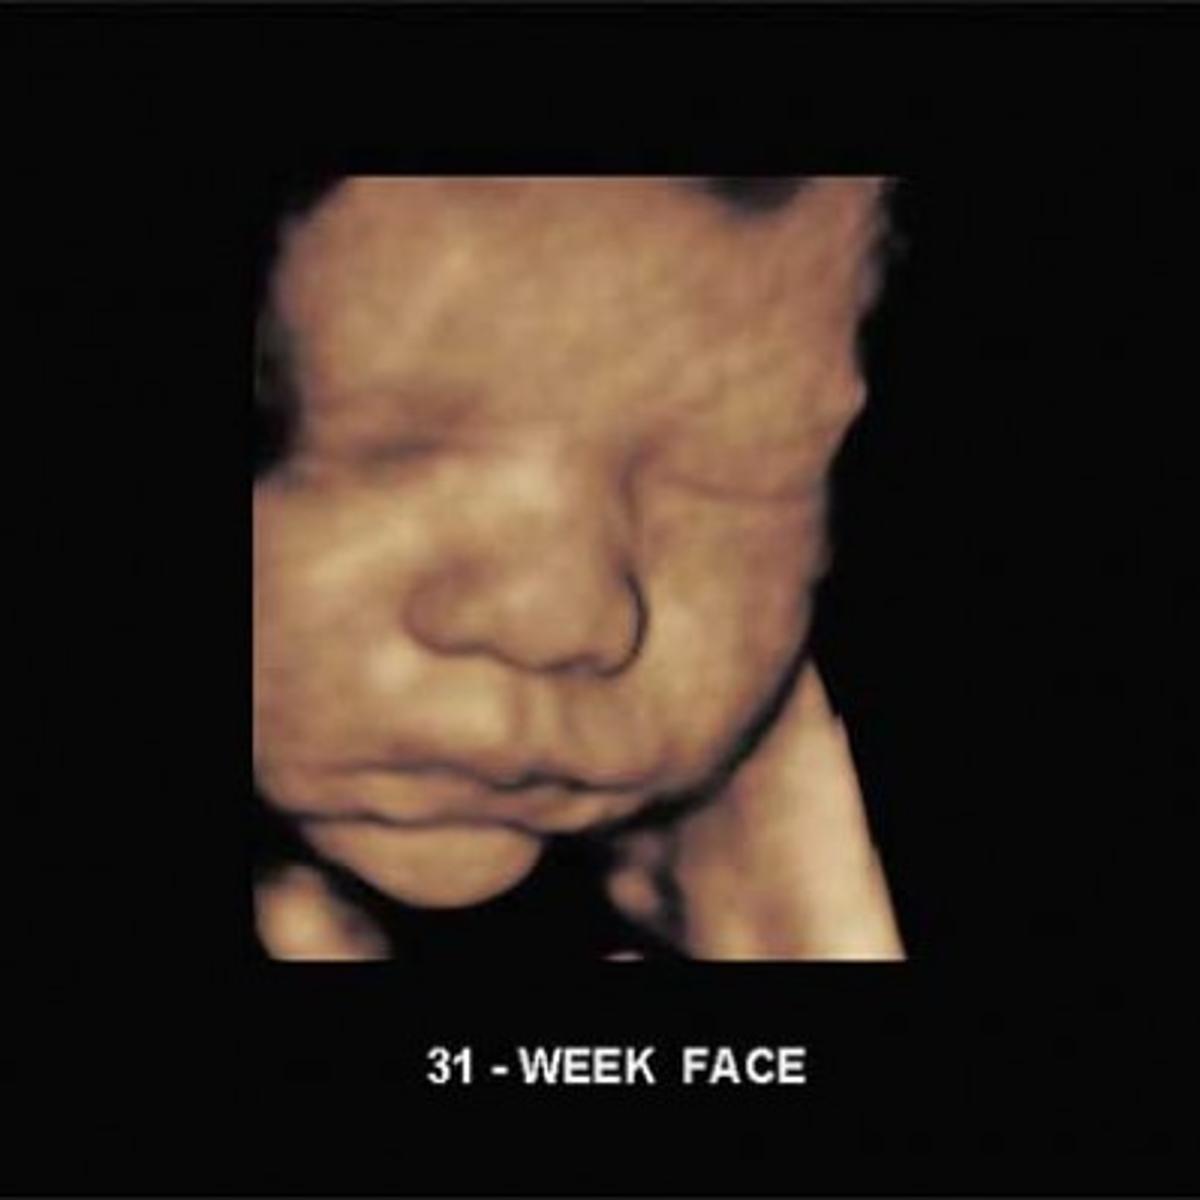

31 Weeks 3d Ultrasound Video

3d 4d ultrasound including luminance imaging at 31 weeks of our adorable little boy.

Ultrasound scan of a baby boy at 31 weeks duration.